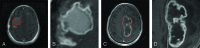

Example of contrast-enhanced T1-weighted MR images of longer term survivors (A and B) with an overall survival of 1405 days and shorter term survivors (C and D) with an overall survival of 447 days. A and C, Contrast-enhanced T1-weighted MR images with tumor contours in red. B and D, Tumor patches segmented from A and C, respectively.